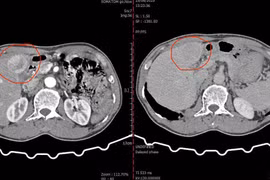

Vi sóng điều trị ung thư biểu mô tế bào gan

Tại Việt Nam, ung thư biểu mô tế bào gan (UTBMTBG) thường có thời gian sống từ 3-6 tháng. Vi sóng là phương pháp dùng nhiệt phá hủy u gan không phải phẫu thuật, không chảy máu, không có biến chứng nặng, mang lại thời gian sống thêm cho BN trung bình là 20,9 tháng.